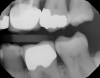

Figure 1 shows a pretreatment photograph of a tooth No. 20. In Figure 2, the circled area of the x-ray indicates the interproximal area where the clinician was uncertain if caries was present. Though x-rays are useful, transillumination is more sensitive and optimal for detecting caries in the early stages.12 With new devices, clinicians can acquire more information before working on the tooth. As shown in Figure 3, caries was confirmed using the transillumination system (CariVu), though it did not show up on an x-ray. The clinician was able to show the image to the patient. The open-tooth camera image then revealed the extent of the caries in the exact position that was displayed in the transillumination image (Figure 4). This is a significant advantage in minimizing preparations and saving valuable tooth structure.

Fig 2. Based on x-ray, clinician was uncertain if caries was present in red circled area.

Figure 2